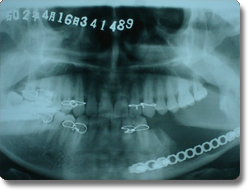

下颌骨肿瘤的手术治疗以往均采用口外颌下区皮肤切口,面部遗留疤痕。我科学习国外的先进方法,运用先进的手术器械,采用经口腔内切口入路方法,对下颌骨良性肿瘤,先行肿瘤切除,再同时采用钛合金成型再造板行下颌骨肿瘤切除后骨缺损缺损的一期修复。该方法的优点是下颌骨肿瘤的切除和骨组织修复再造均经口腔内切口一次手术完成,不再作面部皮肤切口,满足了患者的美容需要。该治疗方法与国际最先进水平保持同步。